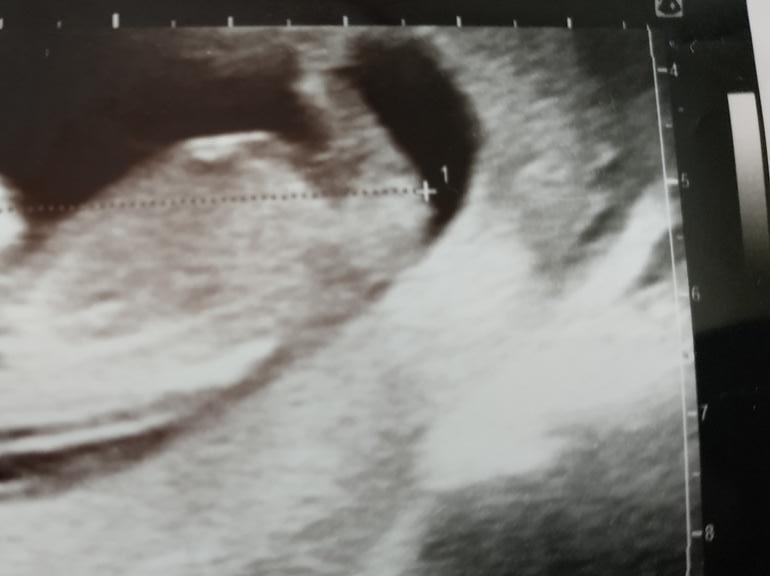

Вот фото с узи, может кто понимает, как они определяют)))) Точно скорее всего мальчик?

Мой мальчик в 12 и 3.

Мальчик 99 и 9 судя по УЗИ вашему . Очень задран половой бугорок . У девочек так не бывает . Мне оба раза в 10 недель правильно про сказали . В этот раз ещё и нипт подтвердил потом